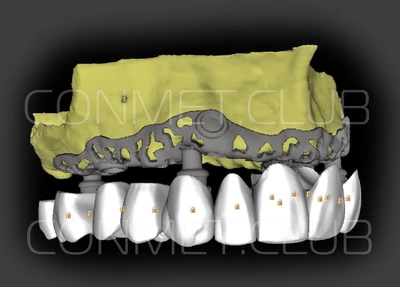

2. После этого произвели компьютерное моделирование самого имплантата и фиксирующих элементов. Примечательно, что в абатментах, использовался отлично зарекомендовавший себя и проверенный десятилетиями интерфейс КОНМЕТ! В результате получили несколько специальных файлов, позволяющих не только сделать сам имлантат, но еще до операции изготовить и сами зубы. Данные файлы передали в изготовление на специальном 3D оборудовании.

Первый вывод к которому мы пришли, это то, что для данных конструкций имплантатов сохранять внутренний интерфейс с шестигранником и конусом Морзе нецелесообразно из-за ограничения возможностей современной 3D печати титана. Кроме того, техническая обработка после 3D печати такого интерфейса представляет значительные трудности и ведет к неоправданному увеличению цены. Поэтому пришли к единодушному мнению, что лучший вариант-это опорные элементы полностью повторяющие абатменты-мультиюниты.

Посмотрите на небольшом клиническом примере новый подход к конструированию имплантата по сравнению с имплантатами описанными в начале этой статьи.

Клинические работы с субпериостальными имплантатами производства Конмет, проведенные в 2019 году, позволили унифицировать интерфейс данных имплантатов под современный цифровой протокол. Более того, необходимые конструкционные элементы были введены в официальную базу под программу Exocad. Что позволило сократить время изготовления зубного протеза до 1-3 дней!